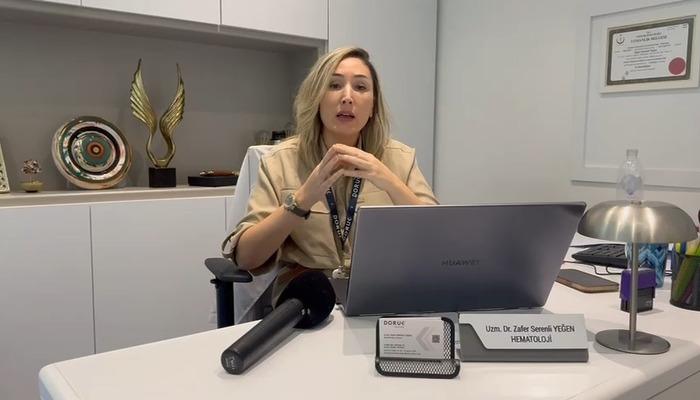

Lösemi de erken teşhis hayat kurtarıyor